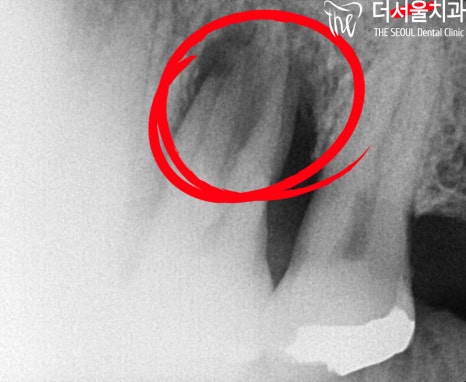

# 14, # 26 소구치 및 대구치에

치주염으로 인한 골소실이

나타난 것을 볼 수 있었습니다.

시커멓게 변해버린 곳이

이미 염증이 나타났었으며,

골소실이 일어난 것이죠.

아무래도 골소실이 심했던 # 26은

3D CT를 통해 더욱 정밀히 계획을 수립하여

진행되었는데요.

얼마나 뼈가 남아있는지,

뼈이식 재료는 얼마나 넣으면 되는지 등